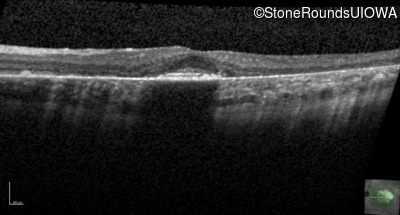

Age at visit: 30 years

This 30 year old man first noticed poor vision in dim light when he was five years old. His visual acuity began to fall in his early 20's.

Macular Disease WDR19 His344Arg CAT>CGT Ser485Ile AGT>ATT AR